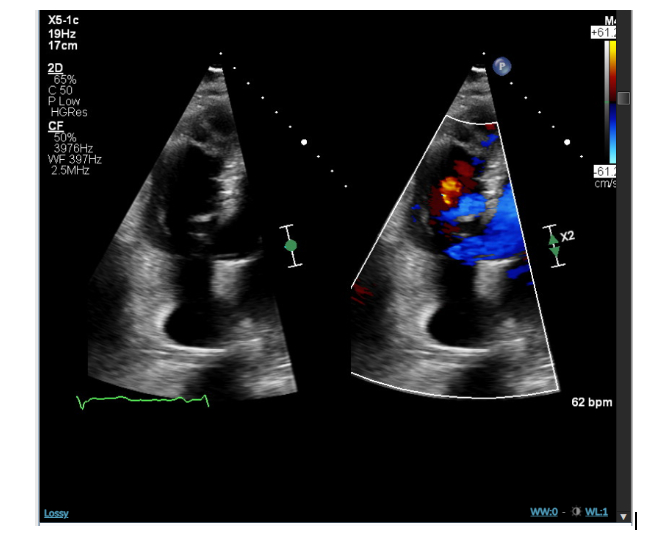

Abstract Body (Do not enter title and authors here): Case description: A 68-year-old man with history of prostate cancer, anal and scrotal squamous cell carcinoma presented to the cardiology clinic with dyspnea on exertion with exercise tolerance limited to 2 flights of stairs. Physical examination showed grade 3/6 holosystolic murmur best heard at the left lower sternal edge. A transthoracic echocardiograph (TTE) revealed an ejection fraction of 65%, prominent muscle bound right ventricular outflow tract obstruction (RVOT) consistent with double chambered right ventricle (DCRV), and a Windsock deformity of the membranous interventricular septum through which there was a VSD with left to right shunting. The maximal pressure gradient across the VSD was approximately 116mmHg. The pulmonary artery systolic pressure was 61mmHg; consistent with severe pulmonary artery hypertension.

DCRV is a rare condition accounting for 0.5 to 2% of congenital heart diseases. It is characterized by abnormal muscle bands that divide the right ventricle into two chambers; a proximal high-pressure and distal low-pressure chamber, leading to progressive right ventricular outflow tract obstruction (RVOT). This condition rarely occurs in isolation and is often ventricular septal defect (VSD), which is seen in up to 90% of DCRV cases. DCRV may go undiagnosed until adulthood. As the degree of RVOT increases, patients present with shortness of breath and decreased exercise tolerance. TTE is an invaluable tool for diagnosing and determining the severity of obstruction through pulsed and continuous wave doppler to measure the gradient across the hypertrophied muscle bundles. Current guidelines recommend surgery in asymptomatic patients with severe right ventricular obstruction with a pressure gradient greater than 40 mmHg between the proximal and distal compartments within the right ventricle. Even though our patient was mildly symptomatic, his significant pressure gradient of 116 mmHg warrants surgical evaluation.